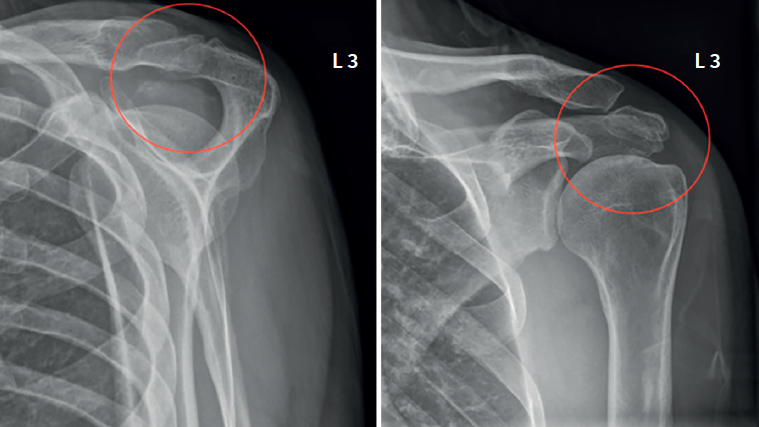

Figure 1. Left shoulder. Preoperative radiographic view showing a "double density" sign (red circle) suggestive of os acromiale.

The basic imaging diagnostic explorations should include anteroposterior, axillary and scapular Y projection radiographs(Figure 1), with the axillary view being the most useful option in this regard(8). Magnetic resonance imaging (MRI) can identify additional disease conditions such as concomitant rotator cuff injury, for example(9). The presence of bone oedema in axial sections in fat-suppressed T2-weighted sequences is an expected sign in the MRI assessment of symptomatic os acromiale (Figure 2).